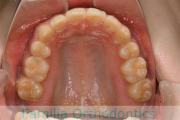

上顎

下顎

前歯の関係など